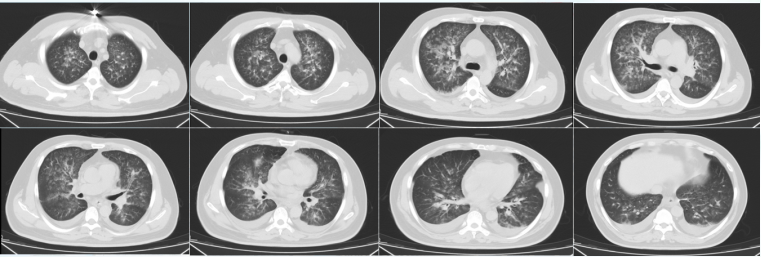

• 胸部CT:双肺渗出性病变,双侧胸腔积液(图1)

1  患者胸部CT(2022-04-18)